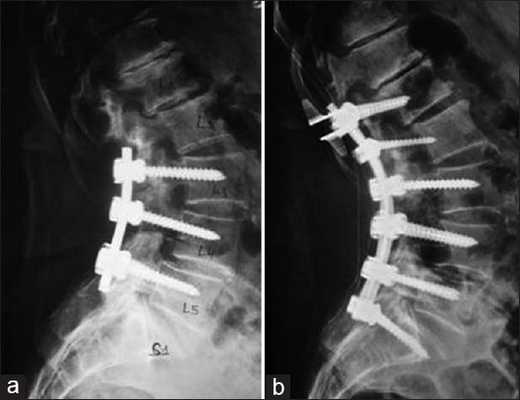

А. При КТ выявлен взрывной перелом тела L1 позвонка с минимальным стенозом позвоночного канала.

Б. При МРТ в режиме STIR также виден перелом позвонка без признаков повреждения заднего связочного комплекса.

Обратите также внимание на наличие очага контузии в конусе спинного мозга.

Данному пациенту была показана только стабилизация перелома без декомпрессии позвоночного канала,

поэтому ему была выполнена чрескожная транспедикулярная стабилизация под флюороскопическим контролем (В - прямая проекция, Г — боковая проекция).

Через 11 месяцев после операции у пациента оставалась лишь слабость тыльных сгибателей правой стопы, походка при этом не страдала.

На контрольных рентгенограммах в прямой (Д) и боковой (Е) проекциях — ось позвоночника не нарушена, проблем со стороны металлоконструкций также нет. Этапы чрескожной установки педикулярных винтов: